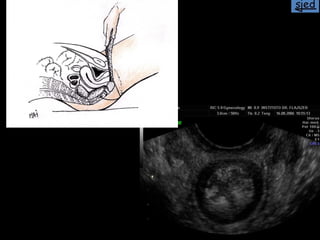

La ecografía ginecológica transrrectal es una ecografía endocavitaria que usa la vía transrrectal en lugar de la transvaginal. Se indica principalmente para pacientes vírgenes con ecografías ginecológicas no concluyentes, pacientes con vaginismo severo o hipotrofia marcada del introito y vagina. La técnica es similar a la ecografía transvaginal pero sin el tope vaginal, y permite imágenes casi idénticas.